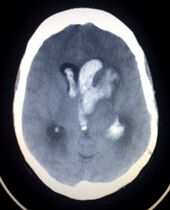

CT scan slice of the brain showing a right-hemispheric ischemic stroke (left side of image).

CT scan showing an intracerebral hemorrhage.